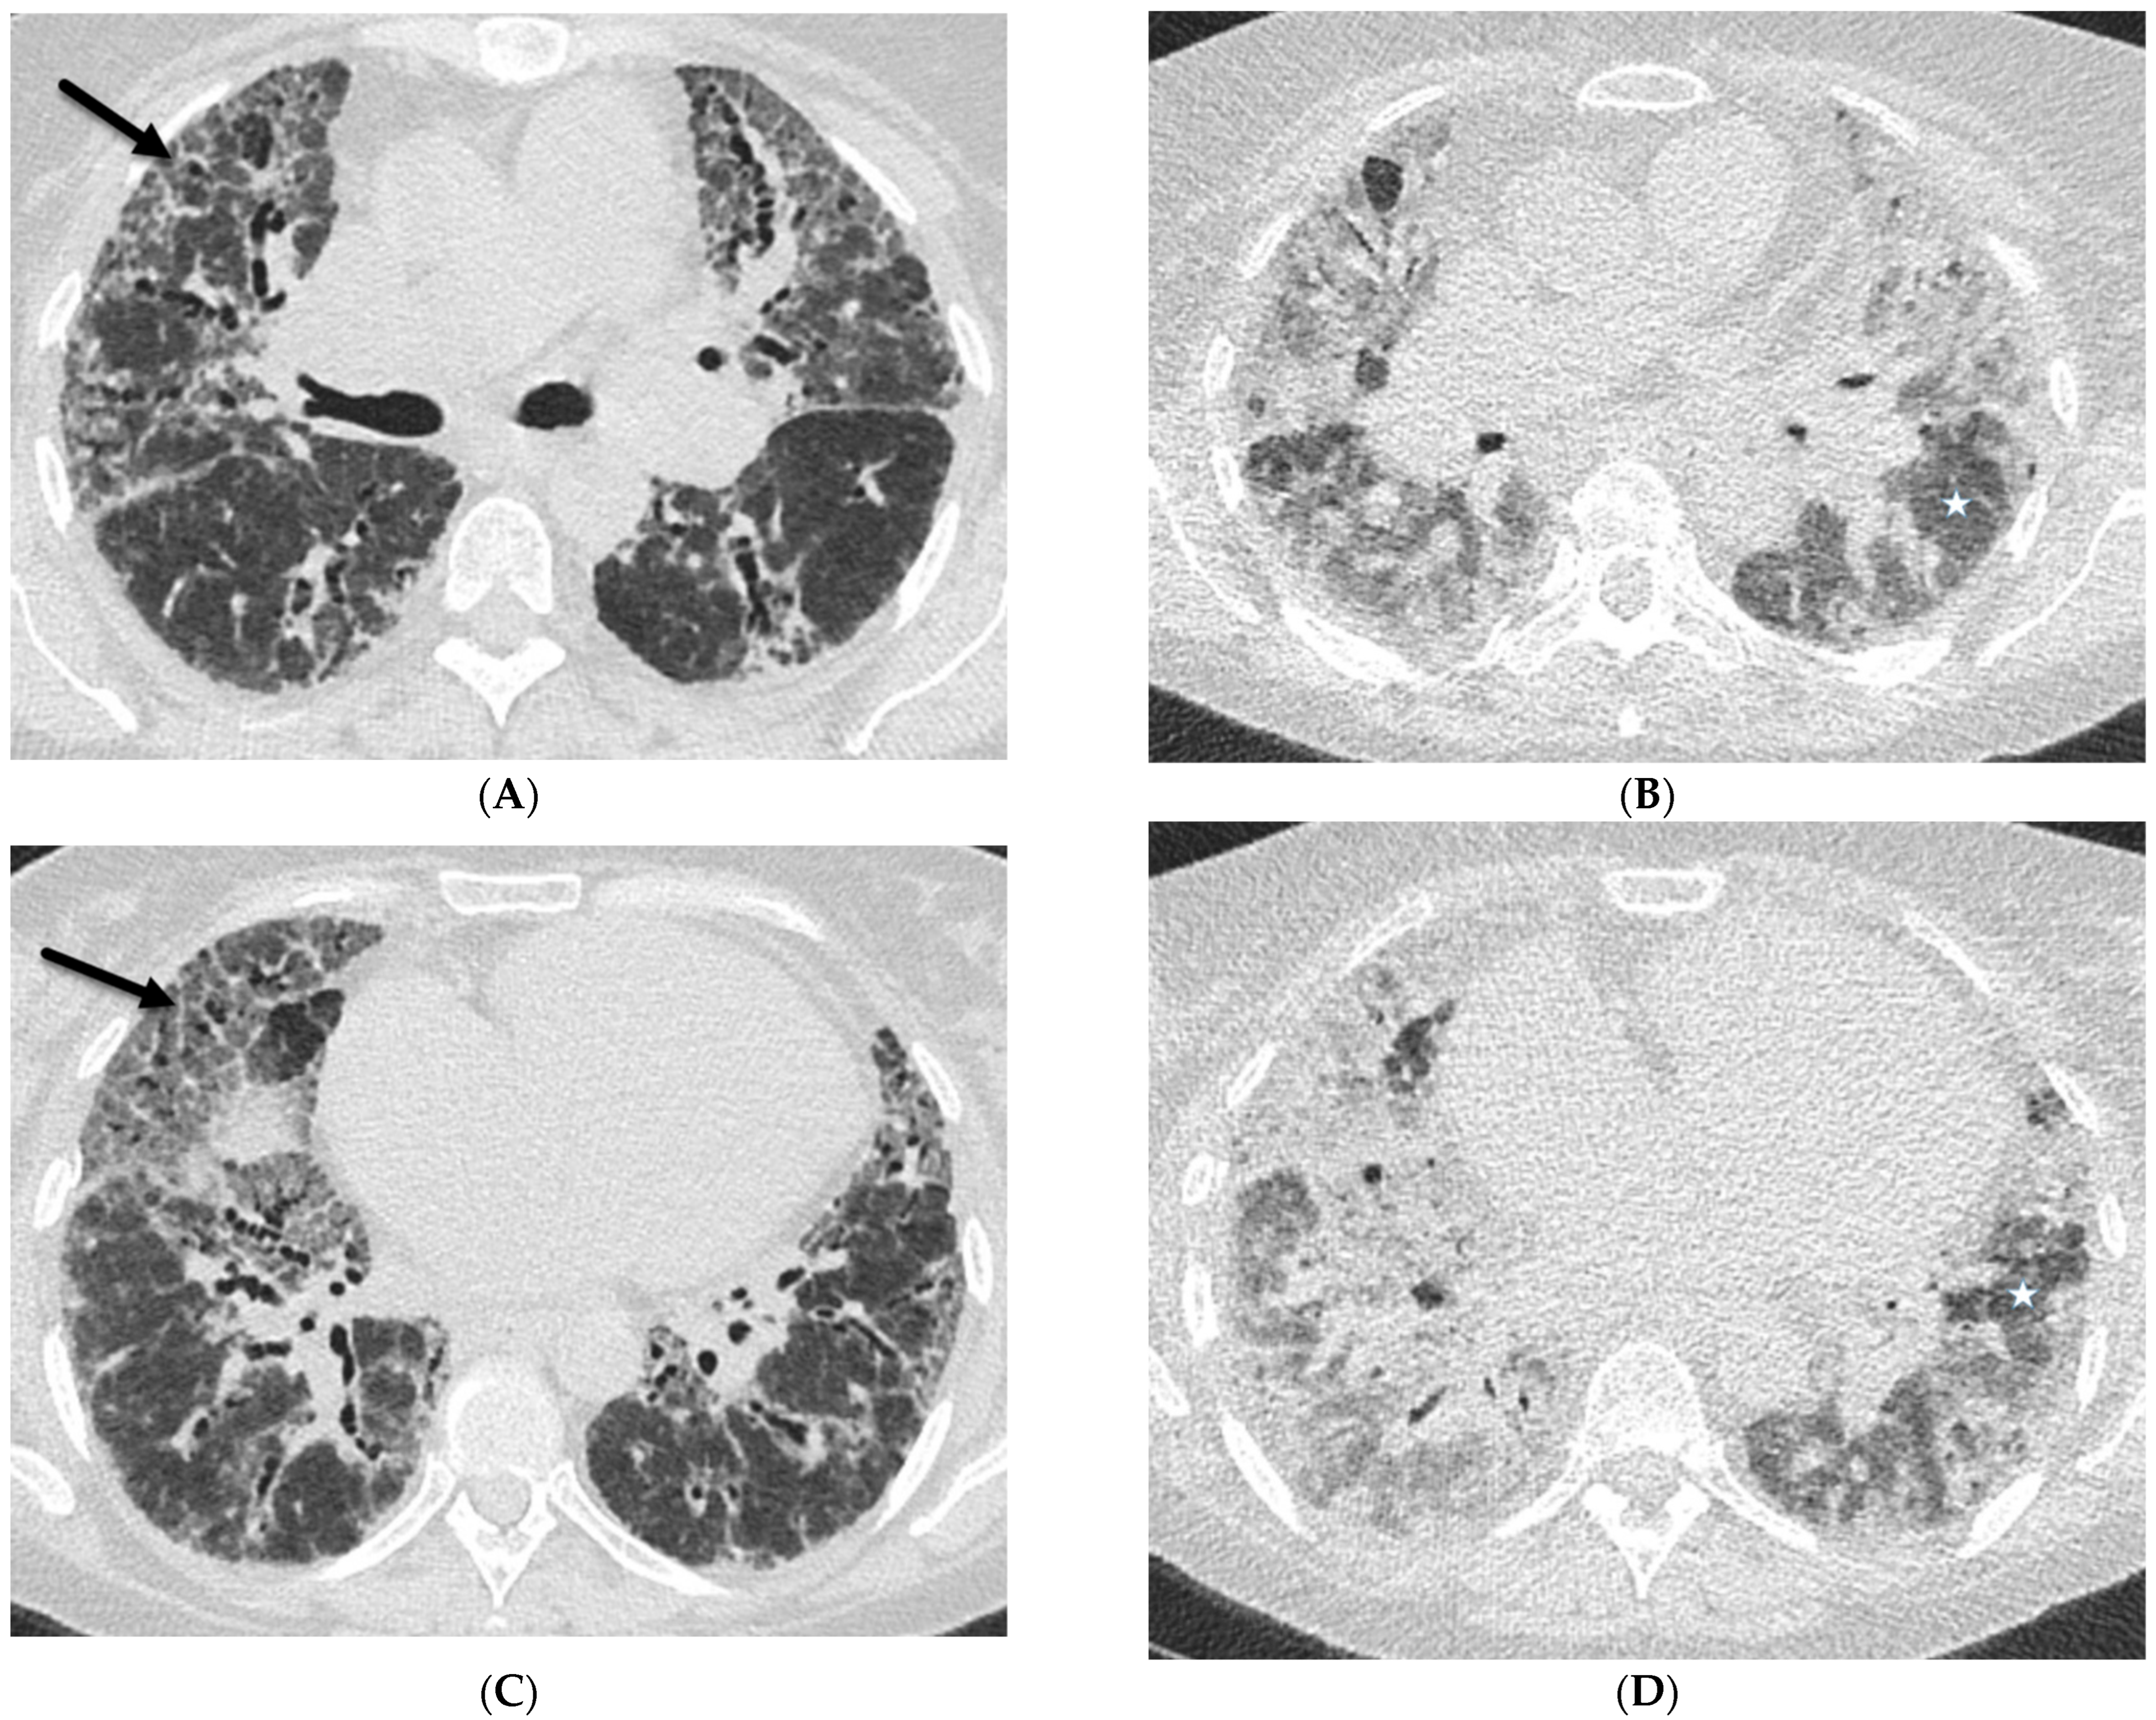

2.1. COVID-19 Pneumonia

2.4. Pneumocystis Jiroveci Pneumonia (PJP)

6.2. Pulmonary Alveolar Proteinosis (PAP)